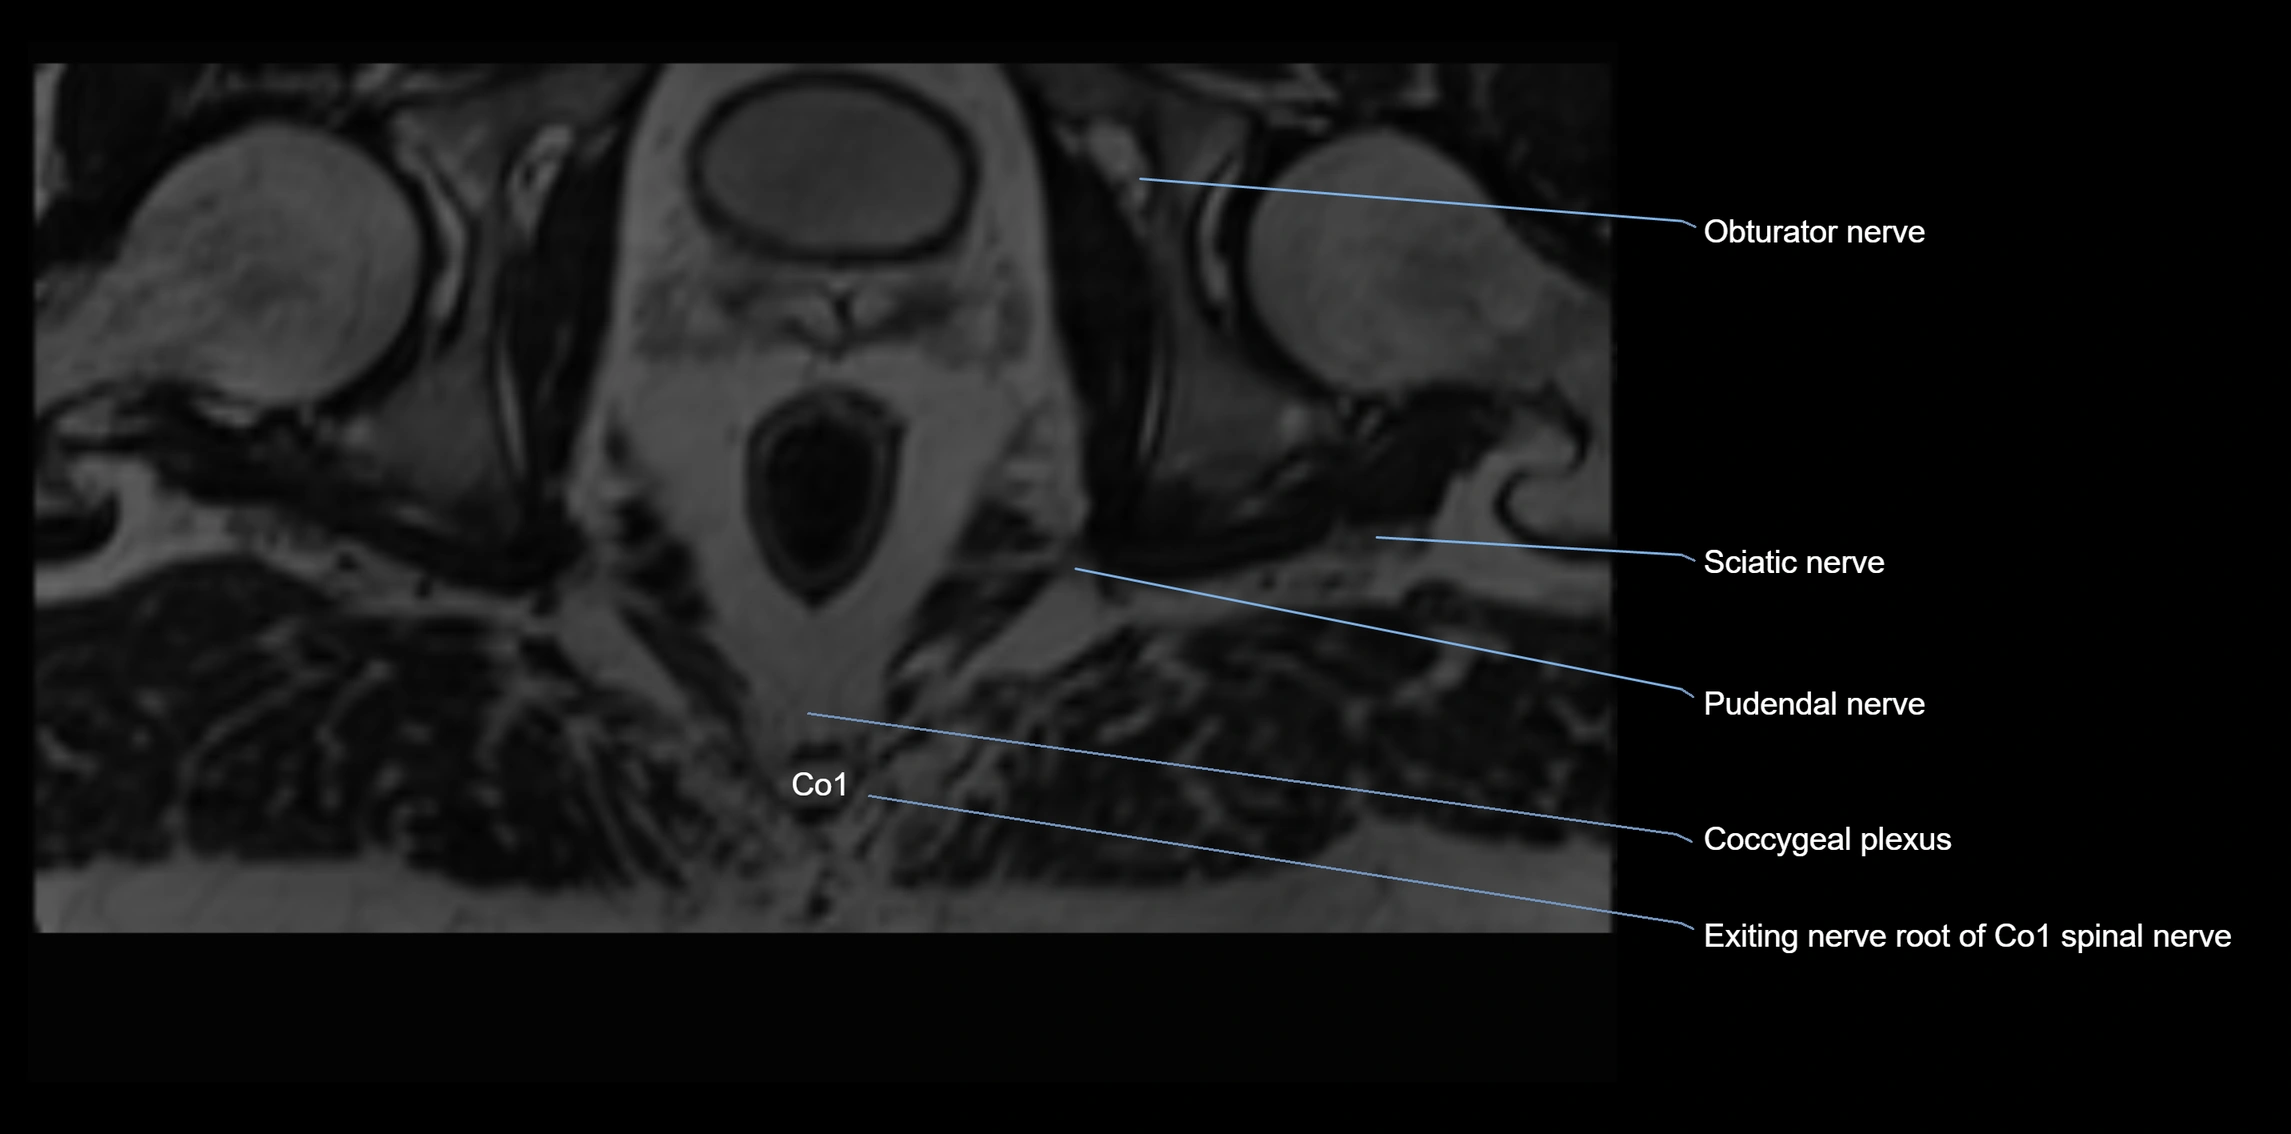

MRI image

image